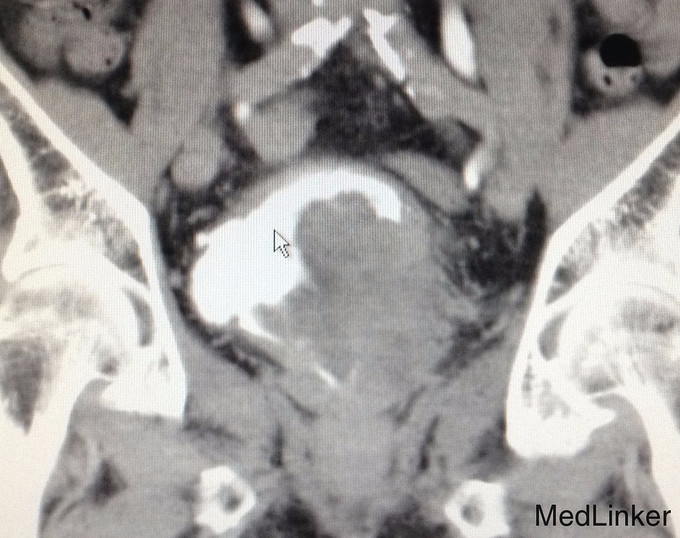

查体:右侧腋窝及右侧锁骨上可触及淋巴结肿大,质硬,移动度差。双侧睾丸缺如。 辅助检查:我院CTU提示膀胱癌,侵犯前列腺及左侧输尿管下段,可疑侵犯右侧精囊腺。